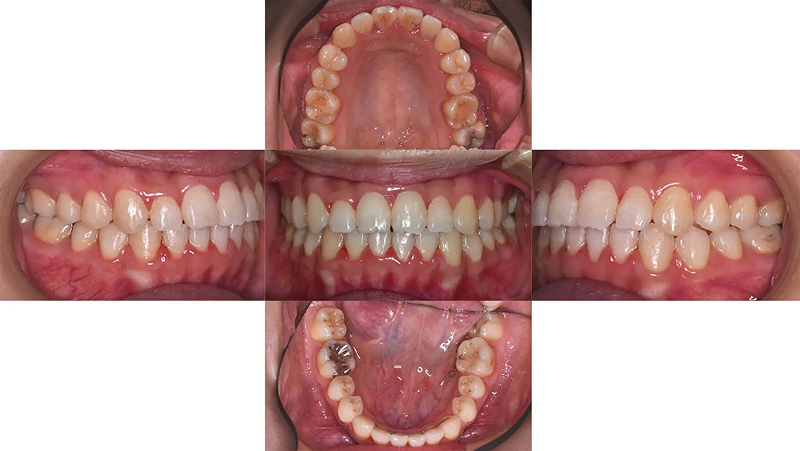

前歯の凸凹が著しい状態でした。清掃がしにくく、上顎側切歯がロックされていました。むし歯治療とともに矯正治療をすることになりました。診査の結果、歯列にスペースがないことがわかりました。口元をきれいにし、歯列を整えるには小臼歯4本抜歯が必要と診断しました。仕事をしながらなので、通院が少し大変でしたが、無事きれいな歯列を獲得できました。

初診 2014.10.16

矯正治療開始 2014.11.26

矯正治療終了 2016.7.12

ファイナル 2016.12.22

治療後2年半 2019.6.24

| 主訴 | 前歯の凸凹を治したい |

|---|---|

| 診断 | 両側アングル1級の叢生 |

| 矯正方法 | 小臼歯4本抜歯を伴うマルチブラケット |

| 矯正期間 | 20か月・21回 |

| 費用 | 746,000円(税別) |

| 調整料 | 月1回 5,000円(税別) |